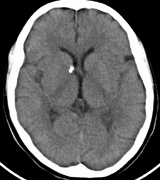

The incidence of optic pathway gliomas in NF1 is difficult to estimate, as the majority are asymptomatic and do not affect vision. In NF1, radiographic evidence of an optic nerve glioma occurs in 15% of patients.64,65 Most tumors are neither suspected historically nor detected by ophthalmic examination.65 Even when optic nerve gliomas become clinically detectable, visual function often remains stable in the absence of any intervention.66,67 Thus routine computed tomography (CT) imaging, even in patients with a known optic nerve glioma, is controversial. The potential risks of repeated radiation exposure in a child with a tumor-suppressor gene defect is a consideration. MRI studies are more revealing than CT but may require sedation or anesthetic and are costly. An MRI is often recommended at the time of diagnosis, but in most cases routine “follow-up” MRIs are unnecessary. Annual ophthalmic clinical examination for relative afferent pupillary defect (RAPD), visual acuity, visual fields, color vision, and funduscopy is usually all that is required, as no therapeutic action is likely to be taken unless there is significant and progressive visual involvement. Optic nerve gliomas may involve the optic chiasm and be associated with endocrine disorders or nystagmus.68–70 Surgical excision of chiasmal gliomas (Fig. 6) carries a high risk of visual loss. Invasion of the hypothalamus or the third ventricle carries a poor prognosis, with greater than 50% 15-year mortality rate.71 One review of radiation treatment for chiasmal gliomas collated data from small case series and found no significant long-term improvement in visual function, progression, or mortality with radiation treatment.71 Other reports suggest that radiation doses over 4500cGy improve symptoms and slow progression of chiasmal gliomas over several years.72 Adequate tumor coverage by radiotherapy results in irradiation of normal brain and nearly all children need hormone replacement.73 Chemotherapy is an alternative.74,75